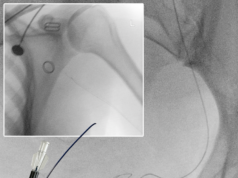

Moreover, Li and colleagues write: “Reducing access site complications is relevant to flow diversion for two reasons. First, flow diversion employs larger bore access systems, which may increase the likelihood of access arterial injury, bleeding or occlusion. Second, prolonged dual antiplatelet therapy is administered to patients undergoing endovascular flow diversion along with heparin, which increases the risk of access site bleeding. Additionally, the smaller diameter of the radial artery raises the question of whether a transradial access approach is uniformly feasible for flow diverting procedures.”